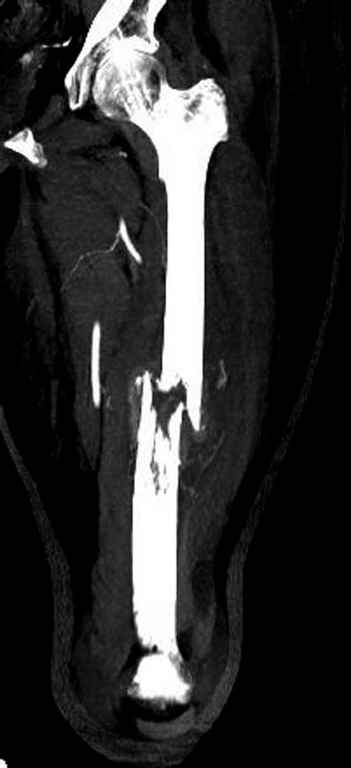

Известно, что многие из нас независимо от метода лечения и стадии первичной опухоли проводят интрамедуллярное штифтование при различных патологических состояниях бедра, включая патологические переломы.

В зависимости от характера опухоли некоторые патологические переломы имеют риск кровотечения во время операции. Множественные литературные данные подтверждают, что надо проявить осторожность при интрамедуллярном остеосинтезе при неизвестных опухолях, особенно где имеется подозрение на Renal Cell Carcinoma. (RCC- hypernephroma) http://www.bonetumor.org/tumors/pages/page64.html

Для предупреждения кровотечения во время рассверливания, за день до операции провели эмболизацию сосудов питающий метастаз. http://radiology.rsnajnls.org/cgi/reprint/150/3/673.pdf (7-11, 12-15-16)

С минимальным рассверливанием и ретроградным методом провели остеосинтез бедра 12 мм гвоздем. (17-20)

Кровопотеря во время операции меньше 100 мл.